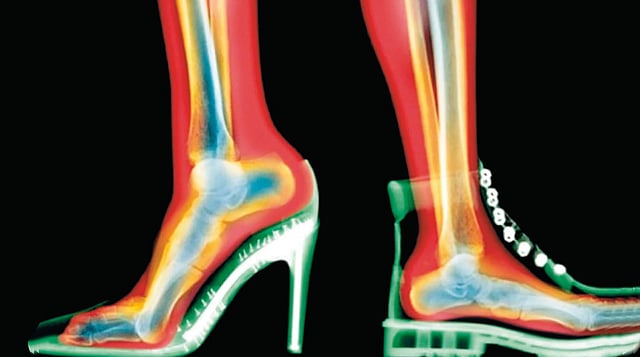

अयोग्य पादत्राणांमुळे पाय, घोटे यांच्या तक्रारीही वाढल्या आहेत. या दुखण्यांचा परिणाम पुढे गुडघे, कंबर आणि पाठीपर्यंत पोहोचतो. याचे कारण आजची अनेक फॅशनेबल पादत्राणे मानवी पायांच्या नैसर्गिक रचनेशी सुसंगत नाहीत.

आजच्या काळात फॅशनच्या विश्वात पादत्राणे किंवा चप्पल केवळ पायांचे संरक्षण करणारे साधन राहिलेले नाही, तर त्या शैली, अभिरुची आणि व्यक्तिमत्त्वाचे प्रतीक बनल्या आहेत. उंच टाचांच्या चप्पला, टोकदार पुढील भाग असलेली पादत्राणे, जड तळाच्या स्नीकर्ससद़ृश चप्पला किंवा साध्या सपाट चप्पला फॅशनचे प्रवाह इतक्या वेगाने बदलत आहेत की, आरोग्याचा विचार मागे पडून केवळ ट्रेंडच्या मागे धावण्याची प्रवृत्ती वाढली आहे.

उंच टाचांच्या चप्पला दिसायला मोहक असल्या, तरी पायांसाठी त्या सर्वाधिक हानिकारक ठरतात. टाच जितकी उंच तितके शरीराचे वजन पुढील भागावर जास्त पडते आणि बोटांवर ताण येतो. त्यामुळे पायाच्या पुढील भागात तीव्र वेदना व सूज, मोठ्या अंगठ्याजवळ हाड उभारले जाणे म्हणजेच गोखरू, बोटे वाकडी होऊन दाबली जाणे म्हणजे हॅमरटो, टाच व घोट्यात वेदना निर्माण करणारा अकिलीज टेंडनचा ताठरपणा तसेच चुकीच्या देहबोलीमुळे कंबर व गुडघेदुखी अशा समस्या वाढतात. टाच जितकी उंच आणि तळ जितका पातळ तितके नुकसान अधिक होते.